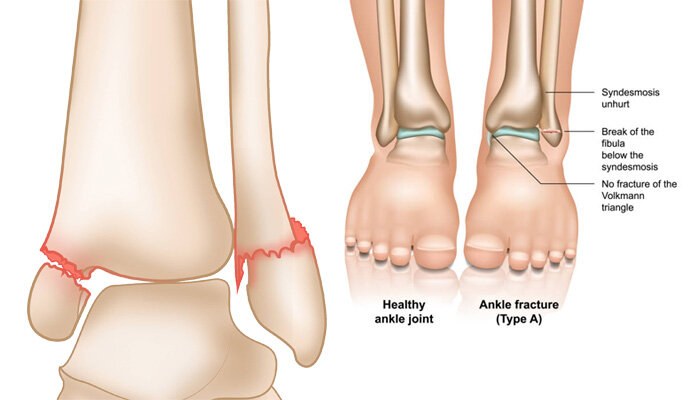

انواع شکستگی مچ پا

بهطورکلی شکستگیهای مچ پا یا با جابهجایی هستند یا بدون جابهجایی. در شکستگی با جابهجایی، استخوان از موقعیت خود خارج میشود؛ اما در شکستگیهای بدون جابهجایی، استخوان در موقعیت صحیح خود باقی میماند. شکستگیهای همراه با جابهجایی عموماً به جراحیهای ترمیمی نیاز دارند.

نوع و شدت شکستگی مچ پا به میزان نیرویی که به آن وارد شده، بستگی دارد. در منابع گوناگون، موارد زیر به عنوان انواع مختلفی از شکستگیها ذکر شده است:

- شکستگی مالئول خارجی: این نوع رایجترین نوع شکستگی مچ پا است. مالئول، برآمدگی بیرونی مچ پا است که در انتهای نازکنی (فیبولا) قرار دارد و زمانی رخ میدهد که مچ پا پیچ بخورد یا به پهلو خم شود.

- شکستگی دوقوزکی یا Bimalleolar ankle fracture: زمانی که قوزک داخلی و خارجی پا دچار شکستگی شود به آن شکستگی دوقوزکی گفته میشود که دومین شکستگی رایج مچ پا است. معمولاً برای ترمیم این نوع آسیب، جراحی نیاز است.